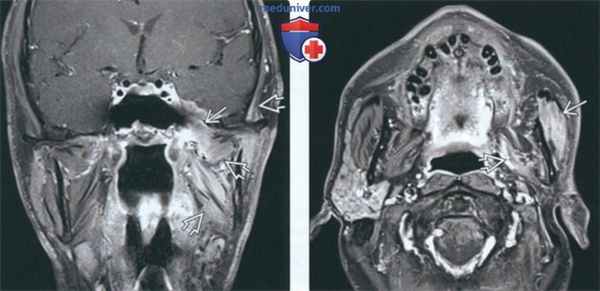

(Слева) На корональной МРТ (Т1 ВИ С+ FS) определяется аде-нокистозный рак, распространяющийся в полость черепа через овальное отверстие. Контрастное усиление жевательных мышц обусловлено подострой денервацией.

(Справа) На аксиальной МРТ (Т1 ВИ С+ FS) у этого же пациента определяется контрастное усиление жевательной мышцы и латеральной крыловидной мышцы, типичное для подострой иннервации. Мышцы начинают терять объем, что свидетельствует о поздней фазе подострой денервации.